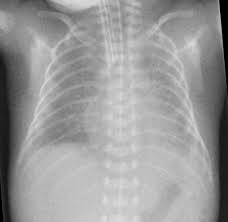

Most babies who now develop chronic lung disease have a birth weight below 1000 g and have only mild early respiratory disease requiring minimal ventilation and low concentrations of inspired oxygen. Advances in both perinatal and neonatal care over the past two decades have improved the survival of very preterm births but morbidity is significant among the survivors1 2 3 Chronic lung disease of prematurity CLD often also called bronchopulmonary dysplasia BPD is one of the most common sequelae in preterm births. Chronic lung disease of prematurity CLDP is also known as bronchopulmonary dysplasia.

Chronic lung disease is defined as oxygen dependency at 36 weeks corrected gestational age. Since 1998 the management of CLD after discharge from neonatal unit follows national guidelines. It can occur when babies are born prematurely and need respiratory.

Most babies who now develop chronic lung disease have a birth weight below 1000 g and have only mild early respiratory disease requiring minimal ventilation and low concentrations of inspired oxygen. Day-to-day care is mostly directed towards improving symptoms with many common interventions. Bronchopulmonary dysplasia is a serious complication of prematurity resulting from poor lung growth and lung injury. However prior to the description in 1967 of bronchopulmonary dysplasia BPD following ventilator therapy for respiratory distress syndrome WilsonMikity syndrome WMS had been described in very preterm infants on minimal oxygen. Chronic lung disease is defined as oxygen dependency at 36 weeks corrected gestational age. Dysplasia means abnormal changes in the. Chronic Neonatal Lung Disease Bronchopulmonary dysplasia BPD first described in 1967 by Northway Defined as O 2 dependence at 28 days post birth Now termed old BPD Post-surfactant era new BPD arrest at the canalicular phase of lung development Definition changed in 1988 to O 2 dependence at 36 wks Incidence of BPD.